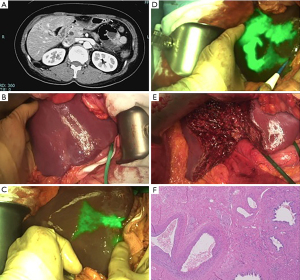

- Segment 5 was then delimited using monopolar energy (Figure 1).

Figure 1 Anatomical S5 segmentectomy. (A) Abdominal CT showing atrophic region in S5. (B) Naked-eye visualization of atrophic region. (C) Near infrared fluorescence imaging showing altered biliary drainage after preoperative ICG administration. (D) Segment 5 demarcation after positive staining with ICG and indigo-carmine. (E) State of the liver after S5 segmentectomy. (F) Anatomopathological findings of sclerosing cholangitis. Hematoxylin & eosin, ×40. CT, computed tomography; ICG, indocyanine green. - Under Pringle maneuver, hepatic parenchyma was transected using the clamp-crash technique. During the procedure, the two major portal branches previously stained were identified and ligated. Tributaries of the right hepatic vein and the middle hepatic vein were also divided.

The anatomopathological report indicated the presence of sclerosing cholangitis (Figure 1).